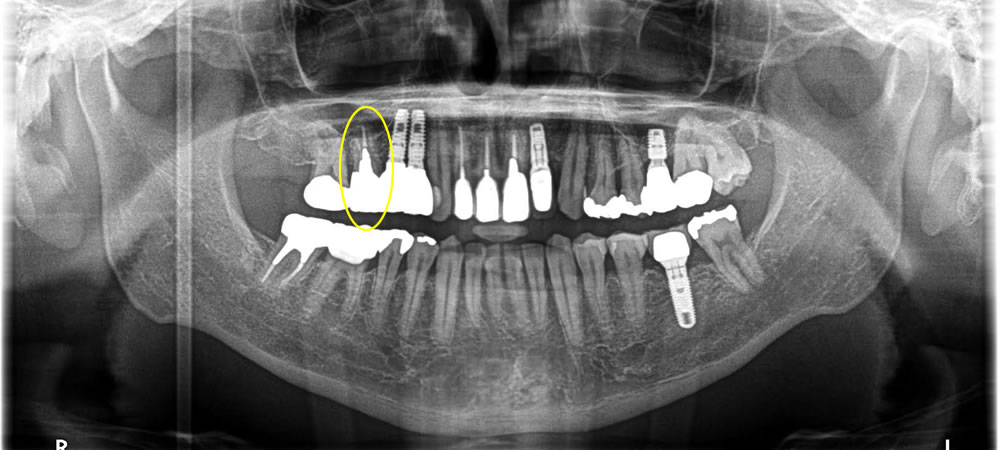

こちらの患者さまはインプラントの後ろの歯が痛いとの事で治療を開始しました。

上部の銀歯を除去したところ、中の歯が虫歯と破折により保存する事ができなくなっていました。

治療方針の相談をしたところ、インプラント治療を希望されました。

手前にインプラントが入っているため、できるだけ歯茎が下がらないように治療をする事と、CT写真にて上顎洞までの骨の厚みが無い事がわかったので、まずは歯を抜いて骨が落ち着くまで4ヵ月待ちインプラントオペを行う事にしました。

今回は上顎洞までの骨の厚みが足りなかった為に上顎洞粘膜を挙上し、骨を作ると同時にインプラント体を埋入していきました。粘膜を挙上する方法としては水の圧力を利用して行っていきました。